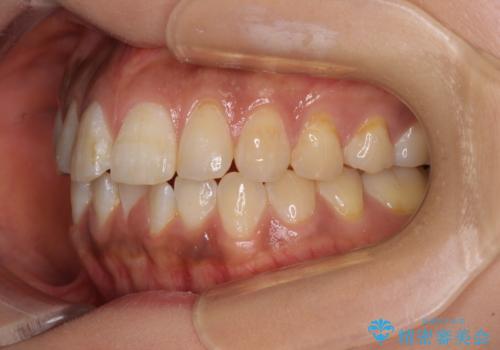

舌のトレーニングをしっかりと行っていただき、上下前歯をしっかりと接触させることができました。

咬合力が強いため、治療途中に奥歯が咬み合わない期間が続きましたが、上下の奥歯でゴムかけを行っていただき、違和感なく咬み合うように仕上げることができました。